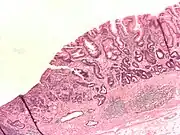

- Gastric adenocarcinoma is a malignant epithelial tumour, originating from glandular epithelium of the gastric mucosa. Stomach cancers are about 90% adenocarcinomas.[67] Histologically, there are two major types of gastric adenocarcinoma (Lauren classification): intestinal type or diffuse type. Adenocarcinomas tend to aggressively invade the gastric wall, infiltrating the muscularis mucosae, the submucosa and then the muscularis propria. Intestinal type adenocarcinoma tumour cells describe irregular tubular structures, harbouring pluristratification, multiple lumens, reduced stroma ("back to back" aspect). Often, it associates intestinal metaplasia in neighbouring mucosa. Depending on glandular architecture, cellular pleomorphism and mucosecretion, adenocarcinoma may present 3 degrees of differentiation: well, moderate and poorly differentiated. Diffuse type adenocarcinoma (mucinous, colloid, linitis plastica or leather-bottle stomach) tumour cells are discohesive and secrete mucus, which is delivered in the interstitium, producing large pools of mucus/colloid (optically "empty" spaces). It is poorly differentiated. In signet-ring cell carcinomas, the mucus remains inside the tumour cell and pushes the nucleus to the periphery, giving rise to signet-ring cells.

_H%2526E_magn_400x.jpg.webp) Poor to moderately differentiated adenocarcinoma of the stomach. H&E stain.

Gastric signet ring cell carcinoma. H&E stain. Adenocarcinoma of the stomach and intestinal metaplasia. H&E stain.

Adenocarcinoma of the stomach and intestinal metaplasia. H&E stain.